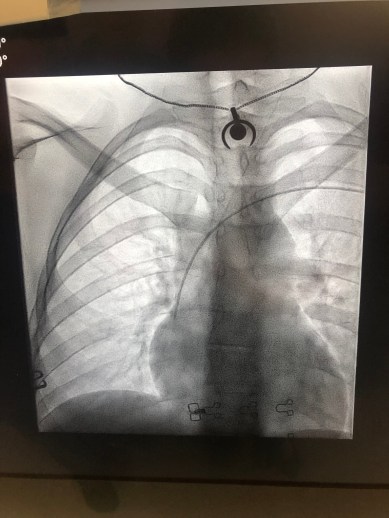

It’s really not a big procedure. After you are given a local anaesthetic, a specialist nurse or doctor places a PICC line into a large vein in your arm and guides it up into the main vein near your heart. They then use an x-ray to make sure everything is where it should be. Here’s a picture of my PICC line right after insertion:

To be honest, getting a catheter was worse than this in my experience. Plus I got a cool picture of my x-ray at the end of it! Gnarly.